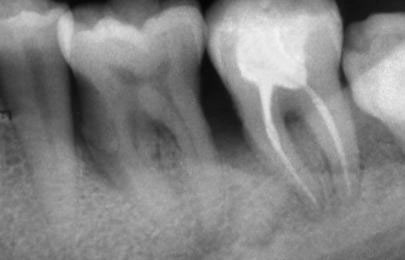

При добре проведено ендодонтско лечение кореновият канал е запълнен точно до стеснението, разположено на 1 - 1.5 мм. от края на канала - т.нар. физиологично стеснение. Не бива да остава незапълнена част от канала. Много често се получава припресване на канлопълнежното средство извън канал на зъба, в тъканите около корена.

Рентгенографии на добре пролекувани зъби